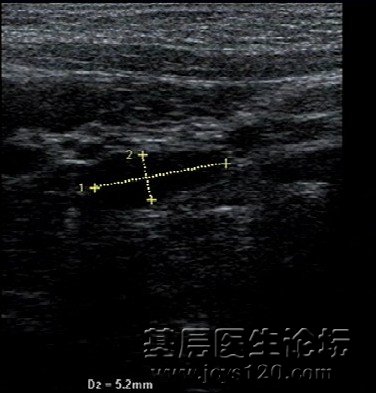

患儿6岁,发热,咳嗽,伴下腹疼痛3天,无恶心呕吐,腹泻等症状,患儿每次感冒后就出现上述症状,给于输液消炎,对症治疗后,感冒症状消失,腹痛慢慢就消失,这次家属为查清上述症状愿意,化验血常规,淋巴细胞数值高,彩超提示,腹腔淋巴结肿大,肝脏,胆囊,胰腺,脾脏声像图未见异常。 最后诊断 感冒后引起 腹腔淋巴结发炎。